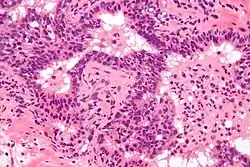

Acute prostatitis is a serious bacterial infection of the prostate gland. This infection is a medical emergency. It should be distinguished from other forms of prostatitis such as chronic bacterial prostatitis and chronic pelvic pain syndrome (CPPS).

Acute prostatitis is relatively easy to diagnose due to its symptoms that suggest infection. The organism may be found in blood or urine, and sometimes in both.[2] Common bacteria are Escherichia coli, Klebsiella, Proteus, Pseudomonas, Enterobacter, Enterococcus, Serratia, and Staphylococcus aureus. This can be a medical emergency in some patients and hospitalization with intravenous antibiotics may be required. A complete blood count reveals increased white blood cells. Sepsis from prostatitis is very rare, but may occur in immunocompromised patients; high fever and malaise generally prompt blood cultures, which are often positive in sepsis. A prostate massage should never be done in a patient with suspected acute prostatitis, since it may induce sepsis. Since bacteria causing the prostatitis is easily recoverable from the urine, prostate massage is not required to make the diagnosis. Rectal palpation usually reveals an enlarged, exquisitely tender, swollen prostate gland, which is firm, warm, and, occasionally, irregular to the touch. C-reactive protein is elevated in most cases.[4]